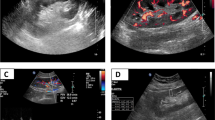

The mean value of KS is calculated and expressed in kilopascals (kPa) and considered indicative of fibrosis (Figs. 1 and 2).

E = 3ρ Vs2, where E is Young’s modulus (kPa), ρ is tissue density (kg/m3), and Vs indicates shear wave velocity (m/s) [11, 13, 14]. In order to calculate Young’s modulus, SWE uses for referencing the density of water (1000 kg/m3). The elasticity is represented by a color-coded image displayed on a B-mode image, where the stiffer tissues are shown in red and softer tissues are shown in blue (Fig. 1) [9, 12].

Ultrasound of the graft and SWE examinations were done using TOSHIBA Aplio 500 machine. Initially, B-mode ultrasound examination was performed for renal allograft with (6C1) curvilinear probe and then shear wave elastographic examination using (14L5) linear probe.

Patients were examined in the supine position. The transducer was covered with ultrasound gel and placed on the skin in a stable position for about 3 s, perpendicularly to better minimize the compression artifact, as shear wave elastography relies on the automatic generation and analysis of shear waves.

Elasticity was then qualitatively assessed using color-coded image superimposed on a B-mode image. At the same time, kidney stiffness (KS) was quantitatively measured; the mean KS value in the region of interest (ROI), as well as the standard deviation (SD) of the measured elasticity, was displayed on the screen and expressed in kilopascals (KPa).

When the cineloop was stable showing parallel lines or parallel circles, we froze the image. Ten measurements of KS using a pre-determined circular regions of interest (ROI = 5 mm) were placed at the nearest region from the skin with a well-represented renal parenchyma.

The mean value of KS was calculated and expressed in kilopascals (kPa) and considered indicative of fibrosis. The information was quantified either as shear wave velocity or as Young’s modulus value expressed in kilopascal (kPa).